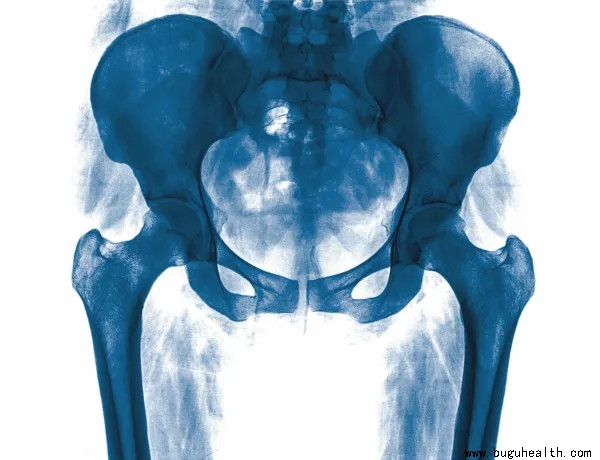

X-线

评估髋关节和腰椎骨性结构的最常用影像学方法。X线是判断髋关节骨骼形状,显示骨骼改变,判断恶性病变以及检查关节间隙和是否发生应力性骨折的最佳工具。